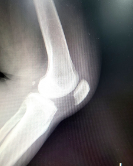

글루코사민은 관절 건강에 도움을 주는 물질 중 하나로, 연골 형성에 필요한 원료입니다. 관절염, 슬관절염, 퇴행성 관절염 등의 질환에서 연골이 파괴되고 손상될 때, 연골을 재생하고 유지하는 데 필요한 물질입니다. 또한, 운동 선수들이 부상 예방과 재활에 사용하는 것으로도 유명합니다. 일반적으로 글루코사민은 콘드로이친과 함께 복용하면 좋습니다. 글루코사민은 식품으로 섭취되거나, 보충제 형태로 복용할 수 있습니다. 하지만, 글루코사민은 약물과 함께 복용시 상호작용이 발생할 수 있으므로 주의가 필요합니다.

1. 연골 건강 개선: 글루코사민은 연골 조직을 구성하는 당질과 단백질의 생산을 촉진하여 연골 조직의 건강을 유지하는 데 도움이 됩니다. 연구에 따르면 글루코사민은 관절염 환자의 연골 손상을 예방하고 연골 조직 재생을 촉진할 수 있다는 것이 입증되어 있습니다.

4. 유연성 향상: 글루코사민은 연골 조직을 유연하게 유지하는 데 도움이 됩니다. 이는 관절 가동 범위를 개선하고 운동 능력을 향상시키는 데 도움을 줄 수 있습니다.